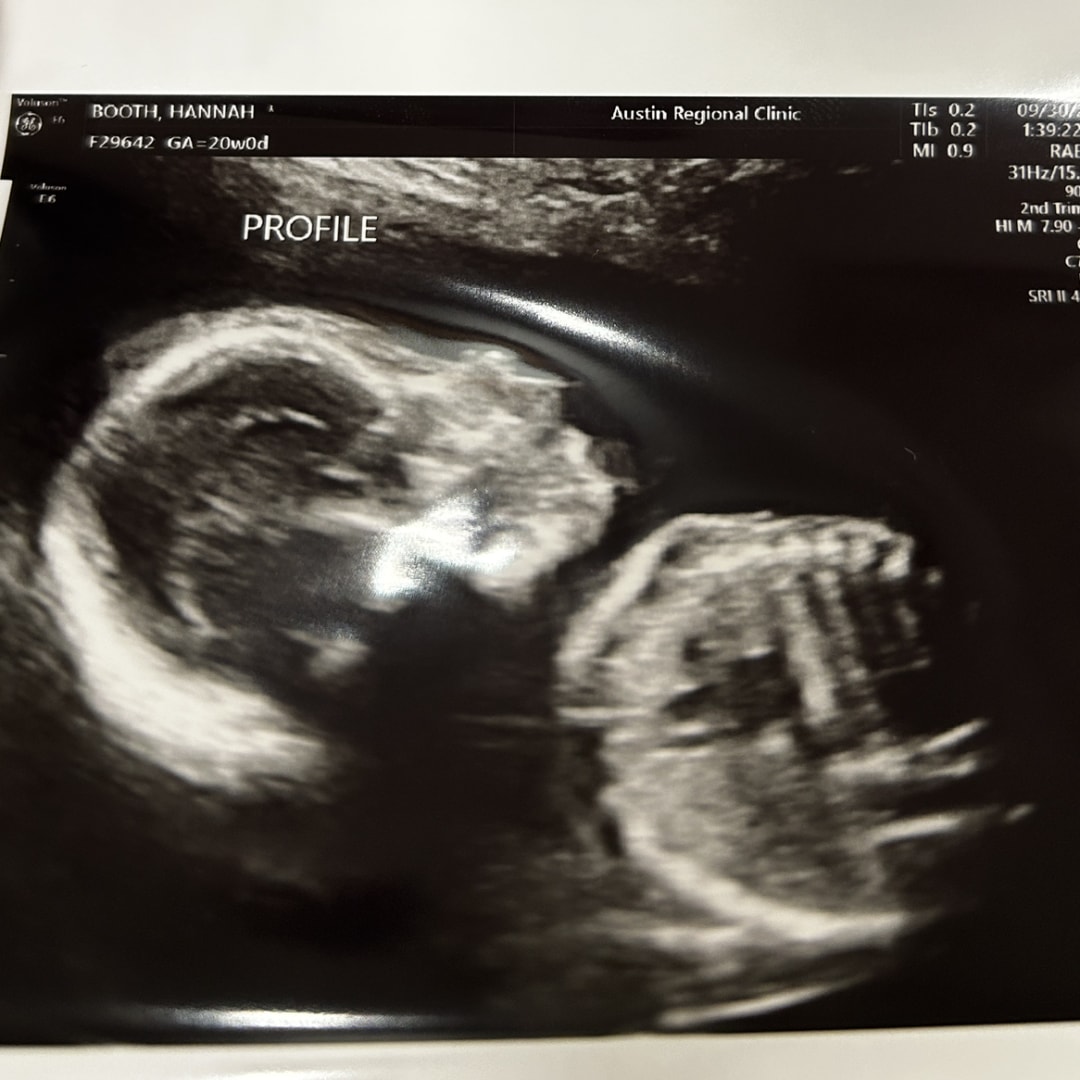

hannah, alec & baby rosemary 🤍Feeding